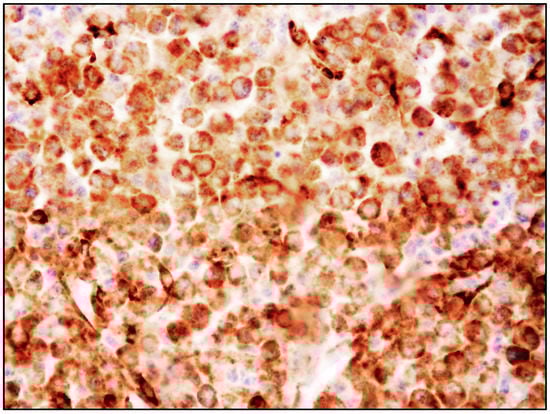

6. MCL: Morphology of MCs

- spindle-shaped MCs characterized by an oval nucleus, elongated cytoplasmic processes and hypo-granulated cytoplasm, often with focal granule accumulation (atypical MC type I);

- well-differentiated MCs characterized by a round-shaped morphology, with a round nucleus and granulated cytoplasm.

- promastocytes which have bi-lobated or multi-lobated nuclei (Figure 2);

- metachromatic, granulated blasts;

- pleomorphic, multinucleated MCs.